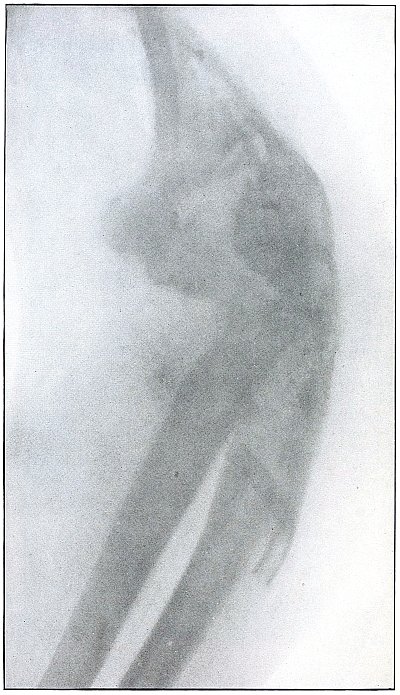

| 20. |

Gunshot fracture, elbow |

50 |

| 21. |